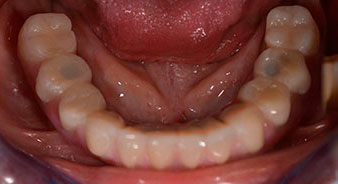

Una volta trascorso il tempo necessario per la osteointegrazione, è stato possibile prendere l'impronta definitiva degli impianti e, poi, è stata realizzata la protesi definitiva (Fig. 19 e 20). A questo punto, il dentista e la paziente hanno potuto decidere insieme se utilizzare delle faccette in ceramica o in vernice acrilica, con una struttura in zirconio o metallo. In questo caso, il Dott. Pascu e il suo team hanno preferito delle faccette in vernice acrilica, a seguito della prognosi difficile sulla dentatura mascellare e sulla posizione allungata del dente 24. Questo tipo di faccette è solitamente molto più facile da adattare e, di conseguenza, può essere modificato per rispondere alla nuova situazione della mascella.

osteointegrazione

Fig. 19

impianti

Fig. 20